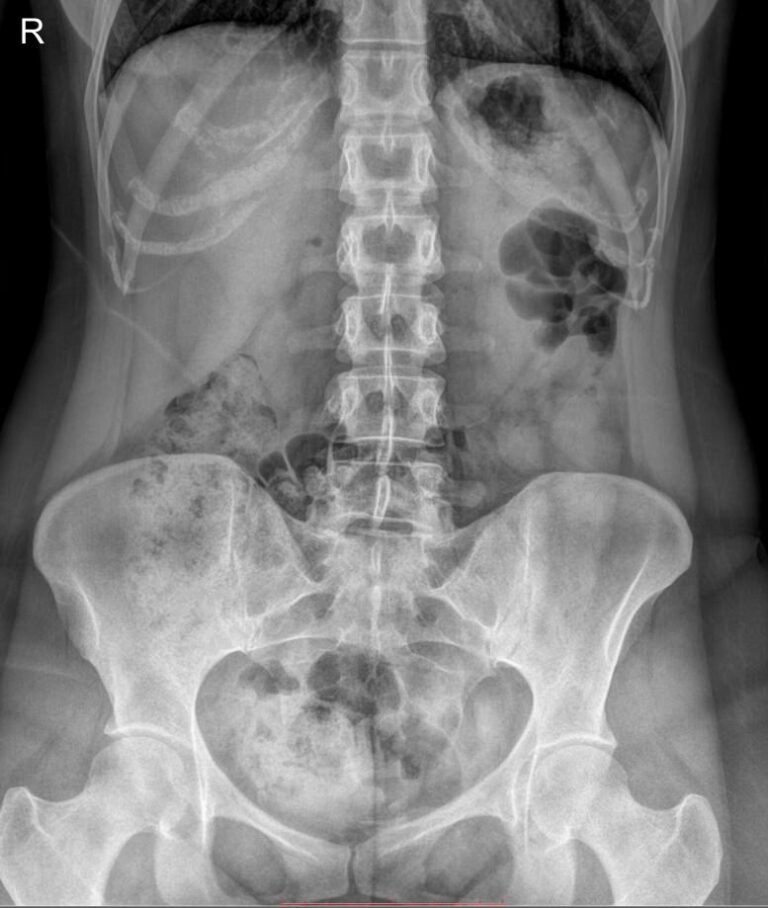

Что показывает обзорный рентген мочевыделительной системы

У здорового человека обзорный снимок покажет:

- Тени почек и мочевого пузыря;

- Мочеточники ― только при значительных изменениях;

- Нижние грудные, поясничные позвонки, ребра, тазовые кости;

- Тени поясничных мышц.

На рентгенограмме будут видны такие патологии, если они есть:

- Увеличение или уменьшение почек в размерах ― признак врожденной аномалии, воспаления и других заболеваний;

- Камни в почках и мочевом пузыре;

- Коралловидные камни в почках;

- Конкременты в желчном пузыре;

- Флеболиты ― камни вен малого таза;

- Опухоли и очаги склероза в костях малого таза;

- Обызвествленные хрящи ребер и лимфоузлы;

- Инородные тела.